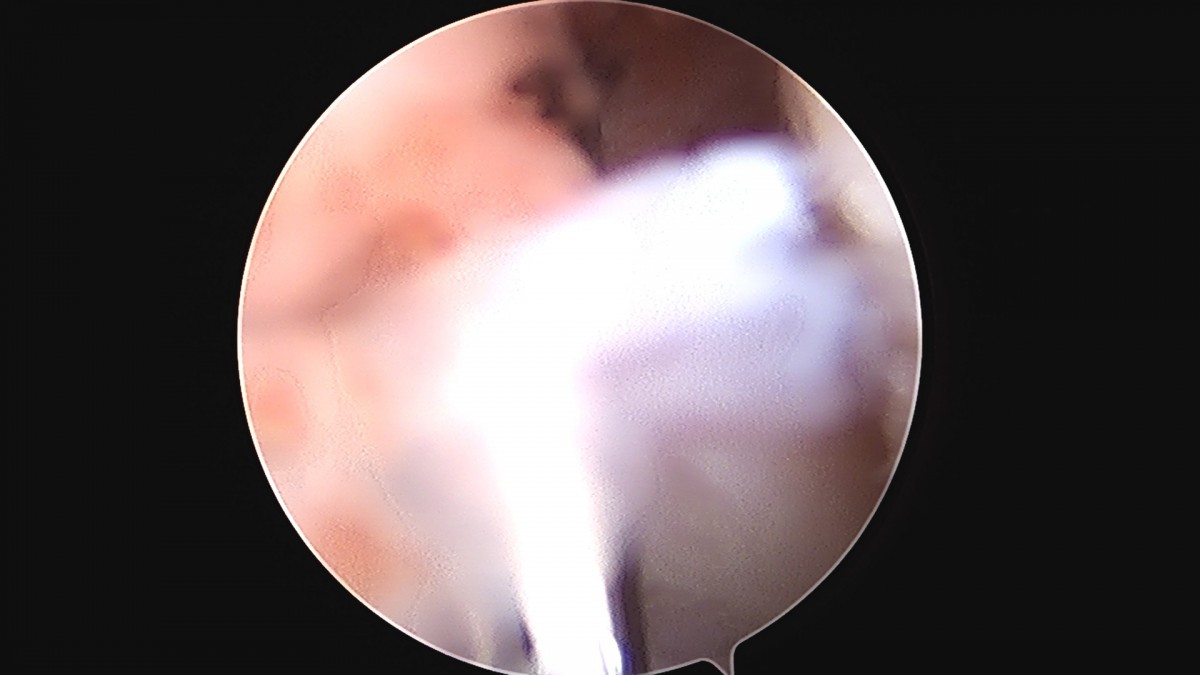

정지영원장님 손목 삼각섬유연골 복합체 봉합술 박현O 환자

작성자 최고관리자 댓글 0건 조회 778회 작성일 25-09-16 16:50